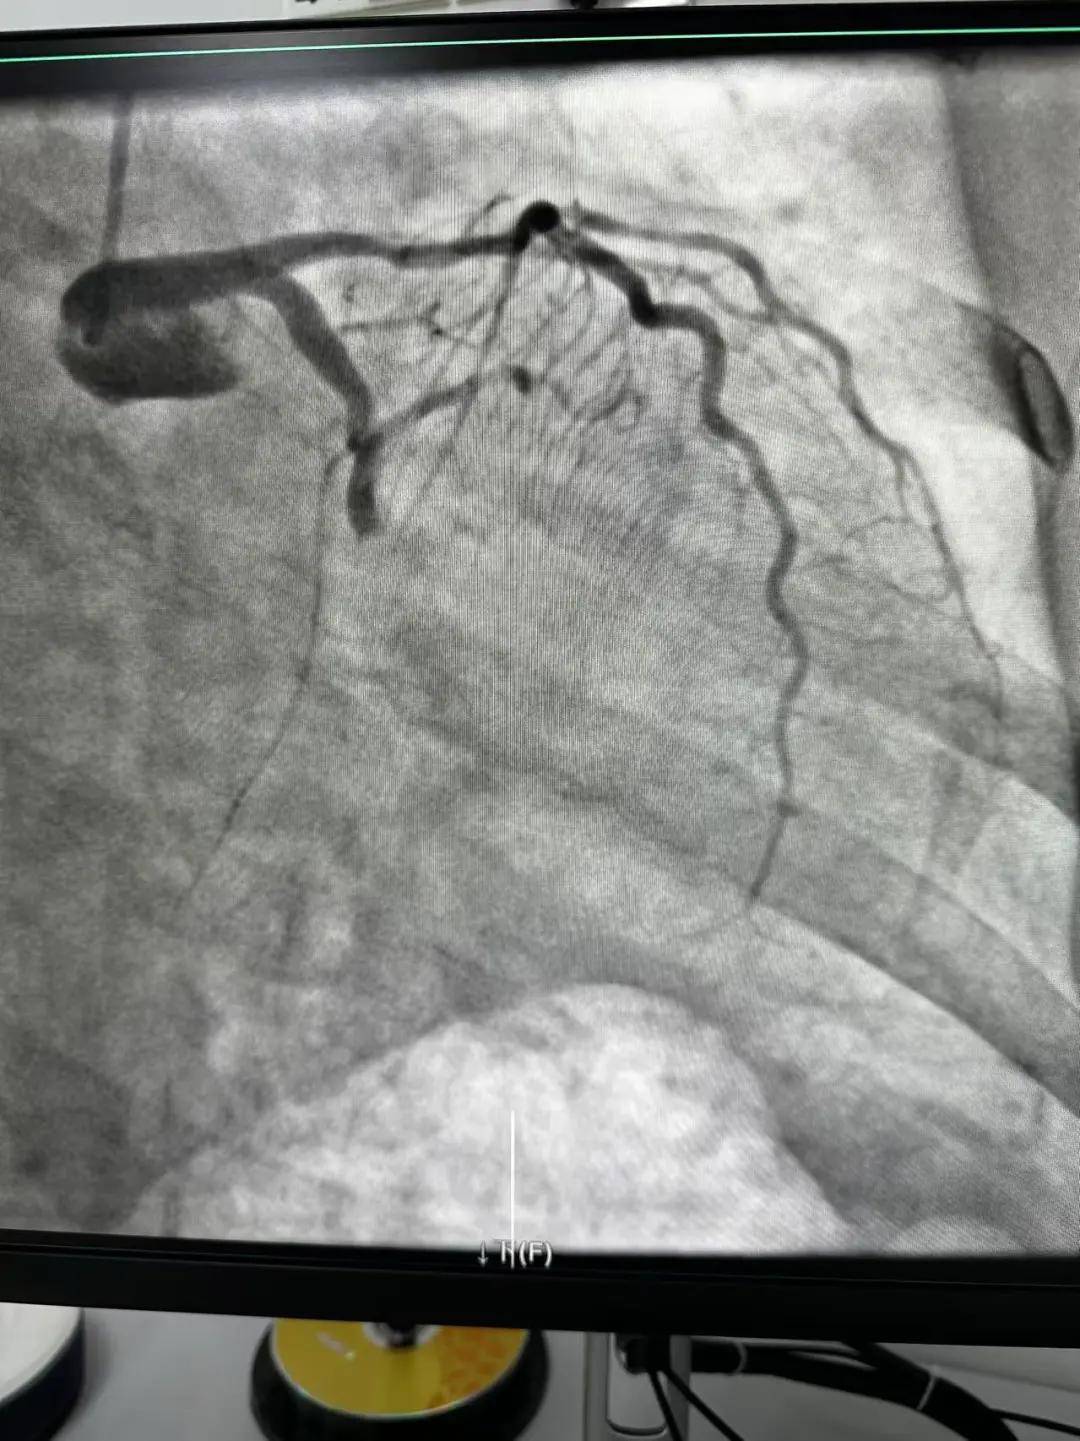

今天最后一臺手術(shù),是一個嚴重三支病變的病人,患者張大爺,71歲,以“突發(fā)胸悶胸痛3小時”為主訴入院。經(jīng)心電圖檢查后示室上性心動過速,以“冠心病、心絞痛、心律失?!睘樵\斷收住入心內(nèi)科。心內(nèi)科團隊通過審慎評估,決定給予患者冠狀動脈造影術(shù)及冠狀動脈內(nèi)支架置入術(shù)。

手術(shù)開臺,在王云峰主任的帶領(lǐng)下,心內(nèi)科團隊為張大爺進行穿刺。由于病人重聽,在手術(shù)臺上配合度不高,加上病情嚴重,導(dǎo)致手術(shù)難度加大。手術(shù)正在緊張進行中,導(dǎo)管室內(nèi)線電話又急促響起!一位急性心肌梗死患者情況危急,需要緊急進行介入治療。

許先生,52歲,大貨司機,在鶴壁至安陽卸貨過程中,突發(fā)胸悶胸痛,伴大汗1.5小時。 患者繞行安陽,于11點38分到達我院大門,11點41分首份心電圖,提示患者下壁心肌梗死。 起病急,病程短,情況十分危險,如果血管完全堵塞將直接威脅患者生命,亟需疏通堵塞血管進行血運重建。

穿刺、造影、放支架……兩個手術(shù)間各個環(huán)節(jié)緊張卻有序地進行著!在心內(nèi)科團隊精準、默契的配合下,兩臺手術(shù)順利完成! 兩名患者的快速、同時、成功救治,得益于殷都區(qū)人民醫(yī)院醫(yī)務(wù)人員快速的應(yīng)急能力、過硬的急救技能,同時更得益于導(dǎo)管室同開臺,保障了救治的迅速有效。